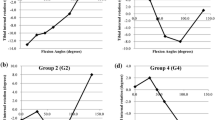

Patient data are summarized in Table 1. The axial rotation angle of the tibia at each angle of knee flexion, in CR knees and PS knees, are shown in Figs. 1 and 2. Both CR and PS knees showed internal rotation during knee flexion. The coronal alignment of the lower limb was slightly valgus during knee flexion (Figs. 3, 4). Each parameter is also summarized in Table 2.